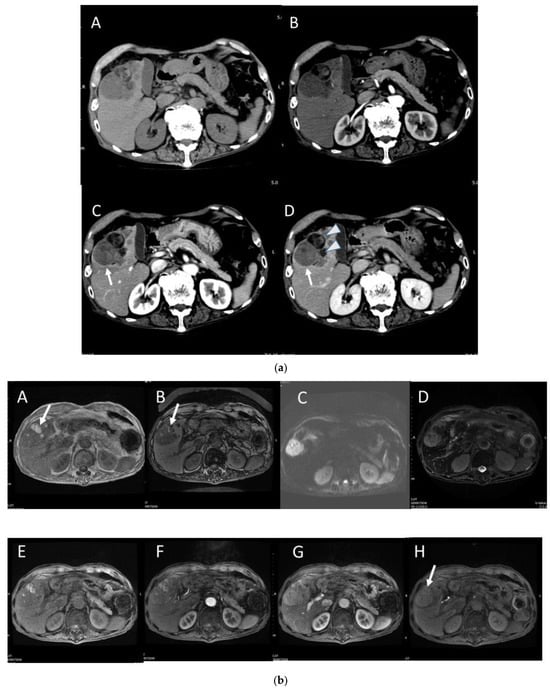

4.7. Combined Hepatocellular and Cholangiocarcinoma (cHCC-CCA)

4.8. Steatohepatitic HCC (SH-HCC)